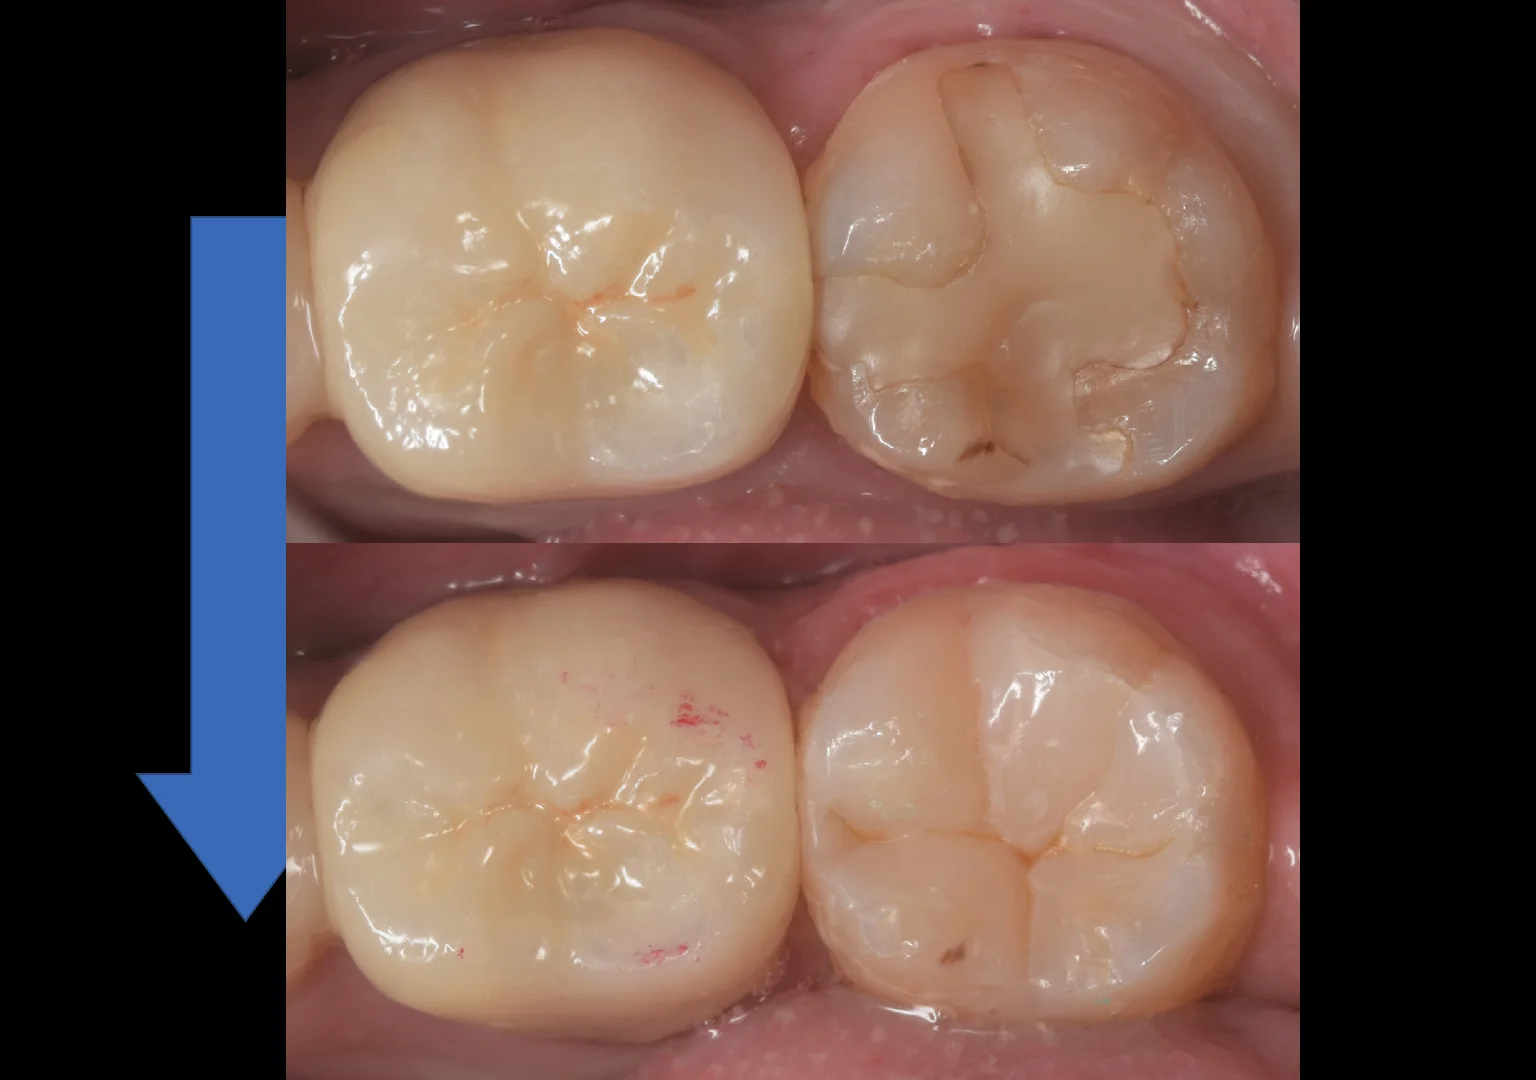

そして詰め終わったのがこちらになります。

手前の歯と似たデザインで仕上げました。

比較的違和感は少なくできたかなと思います。

治療の術前術後はこちらになります。